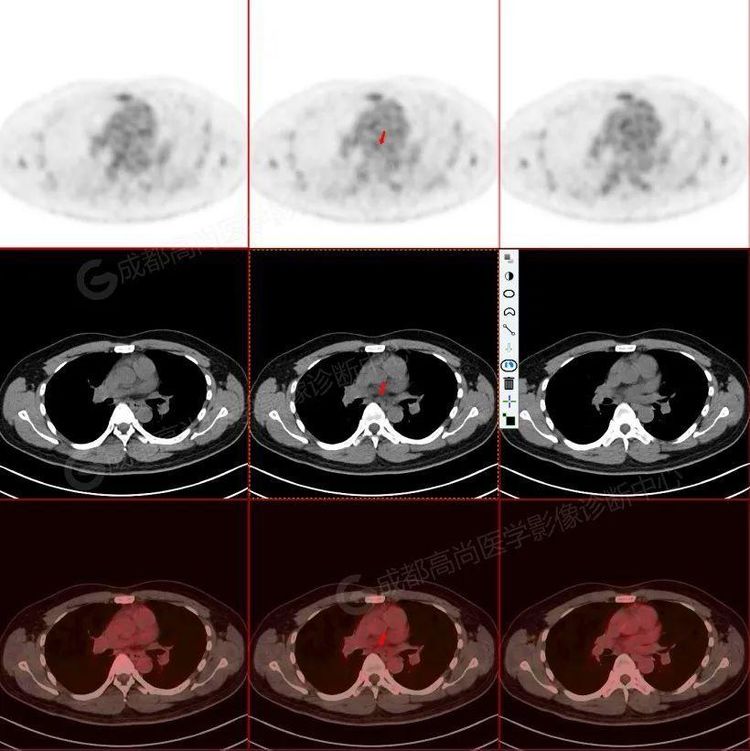

高尚病例:少见的原发性骨淋巴瘤 pet/ct 显像一例

图片尺寸1080x992